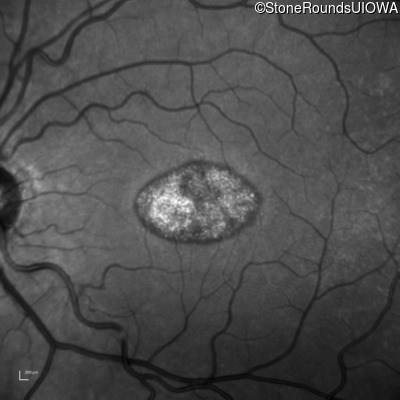

Infrared Fundus Photograph - Left - 20/100 -2 sc

Exemplar